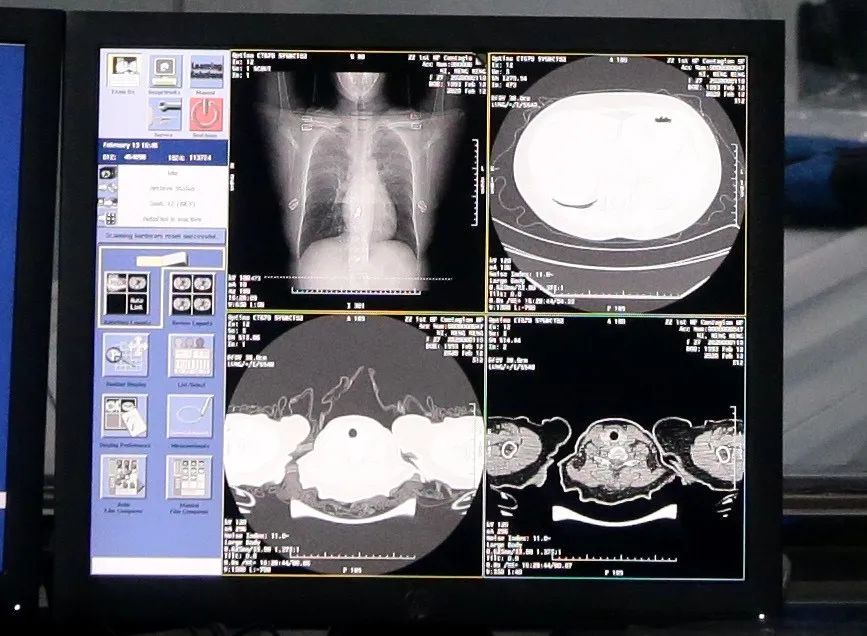

军队越是现代化,越是智能化,越要求作战行动以及装备系统实行标准化。前不久,战“疫”前线传来好消息,阿里达摩院最新研发升级的AI算法诊断技术,能在20秒内对新冠肺炎疑似病例CT影像做出判读,且准确率较高,相比之下,人类医生对一个病例的CT影像肉眼分析耗时大约为5-15分钟。可以看出,AI算法诊断技术有望提高诊断效率,有效减轻一线医生的工作压力。